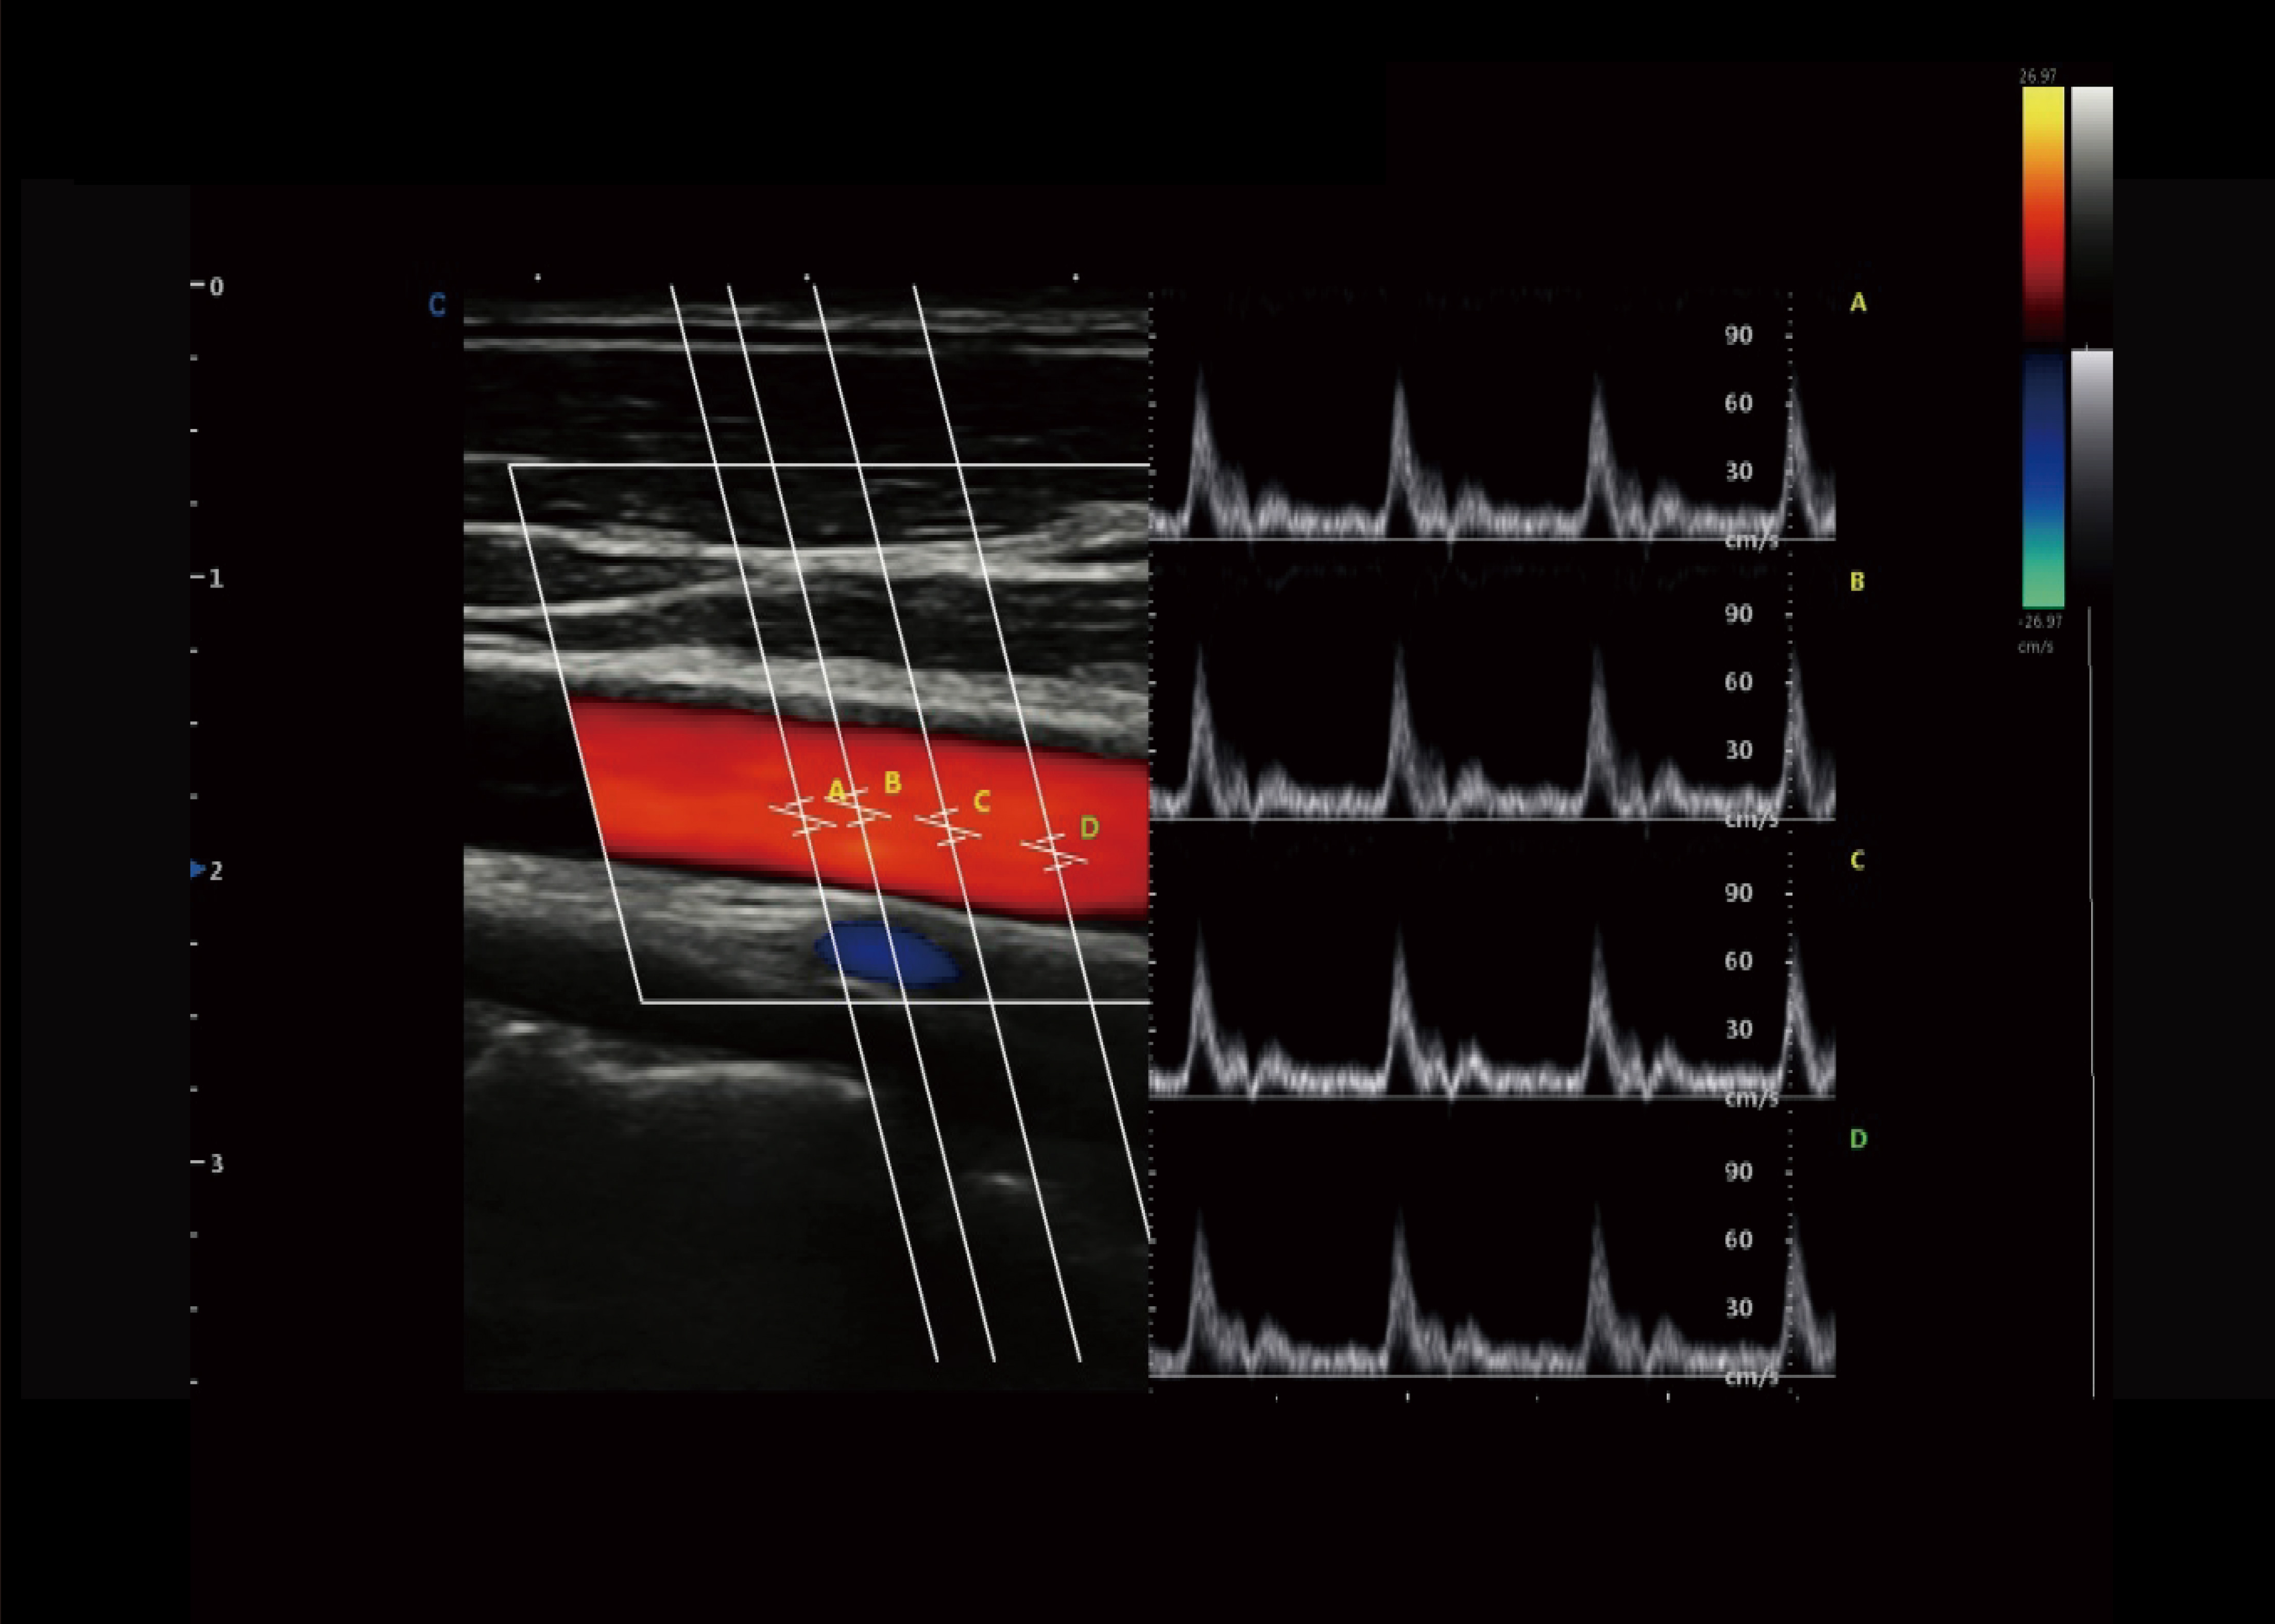

SonoPW

● Im PW-Modus kann das Sample Gate auf 4 erweitert werden.

● Es kann jedes Abtasttor schalten und aktivieren, um ein Mehrpunktsystem zu realisieren.Spektrumsmessung im selben Herzzyklus bei gleicher Scan-Ebene ;Unterstützt synchrone Anzeige des Spektrums und Geschwindigkeitswert.